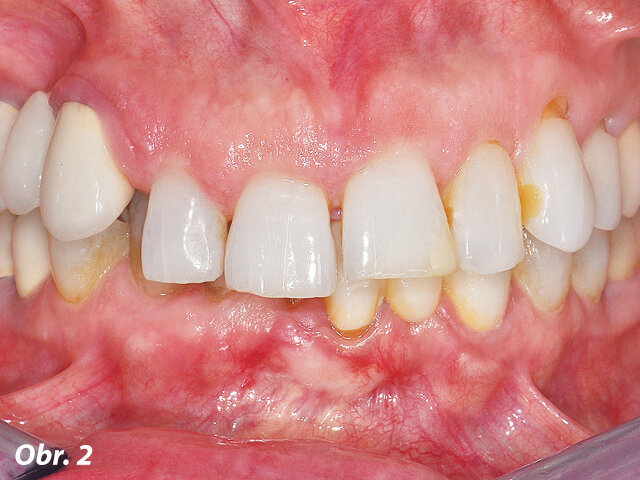

Parodontolog a kolega z ITI, jejichž praxe je dvě hodiny od té naší, doporučili našemu týmu tuto pacientku. Nejdříve byla vyšetřena protetikem dr. Harrym Randelem a následně parodontologem dr. Robertem Levinem pro zajištění týmového přístupu k řešení jejího selhávajícího chrupu. Pacientka se dostavila do naší ordinace jako 65letá nekuřačka (ASA 3: kompenzované nemoci: úzkost/deprese, osteoathritida, fibromyalgie, hypothyreóza a v minulosti myofaciální bolestivá dysfunkce, obr. 1–3). V minulosti si prošla problémy s TMK (např. lupání a bolest v pravém TM kloubu), které jsou v současnosti pod kontrolou a nebolestivé.

Hlavním požadavkem pacientky bylo vylepšení svého estetického vzhledu a komfortu s přáním permanentního a rychlého řešení jejího selhávajícího chrupu. Ve finálním ošetření si rovněž přála redukci gummy smile ve frontální části maxily. Dostavila se do naší ordinace ke třetí chirurgické konzultaci ohledně imediátního zatížení maxilární a mandibulární hybridní rekonstrukce prostřednictvím terapeutického konceptu Straumann® Pro Arch (šikmé zavedení distálních implantátů umožní vyhnout se anatomickým strukturám jako sinus maxillaris, foramina mentalia mandibulae). Tento terapeutický koncept zredukoval potřebu komplementárních chirurgických zákroků a množství implantátů potřebných pro zhotovení fixní hybridní rekonstrukce v rozsahu prvních molárů. Při širokém úsměvu byla zaznamenána střední až vysoká retní linie s dvojúrovňovou okluzní rovinou. Rovněž byla registrována supraokluze horních a dolních frontálních zubů (FDI: 12, 11, 21, 22 a 41–43, US: 7–10 a 25 až 27) vytvářející hluboký skus 6 mm (obr. 2). Ve vzájemném vztahu špičáků byla zaznamenána I. An-

gelova třída s předkusem 6 mm a překusem 6 mm. Vzhledem k hyposalivaci související s její medikací byly pozorovatelné generalizované rekurentní kazy. Hloubka sondáže parodontu se pohybovala od 4 do 7 mm v horní čelisti a od 4 do 6 mm v čelisti dolní s mírným až těžkým krvácením marginální gingivy v obou čelistech. U zubu 6 (FDI: 13) byla klinicky zjištěna vertikální fraktura. Zuby horní čelisti vykazovaly silnou viklavost pohybující se mezi 2.–3. stupněm: 3, 7–13, 20–26 a 29 (FDI: 16, 12, 11, 21 až 25, 31–35, 41–42 a 45). Její profilování z hlediska compliace se svým předchozím zubním lékařem bylo dobré, avšak udávala, že vždy mívala „problémy se svými dásněmi.“

Předběžný terapeutický plán diskutovaný při iniciální návštěvě s pacientkou a jejím manželem zahrnoval následnou diagnózu: generalizovaná mírná až pokročilá parodontitida; generalizované rekurentní kazy vztahující se k suchosti v ústech související s její medikací; zkrácené zubní oblouky s poruchou vertikálního rozměru okluze („mutilovaný chrup“). Prognóza: všechny přítomné zuby nemají naději na záchranu.